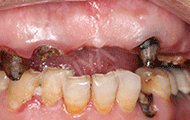

作为一个过来人,我要呼吁理性美牙!我这半口的残根烂冠,是因为十来年前的烤瓷牙冠造成的,以前的审美流行烤瓷牙,用来美白牙齿,让牙齿好看,年轻人都爱美,我就做了这半口的烤瓷牙冠,问题在于这烤瓷牙和真牙的密合度有限,而且打磨了我很多真牙,现在自己的真牙也坏了,要拆掉牙冠,发现自己的牙齿都不能用了。现在种牙,就为了自己后半生的口福。